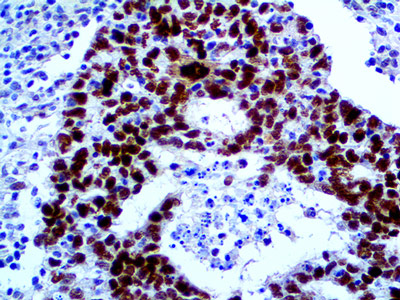

SOX-10

SOX-10 est un marqueur très sensible pour les mélanomes (97% contre 91% pour le S-100). Il est particulièrement sensible pour les mélanomes desmoplastiques qui sont souvent difficiles à détecter par d’autres marqueurs de mélanocytes. SOX-10 est modérément à fortement exprimée dans les mélanomes...